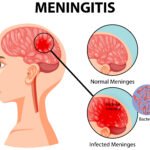

- Meningitis